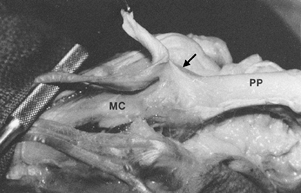

Figure 49.8. Extensor insertion into the dorsal MP capsule and dorsal base of the proximal phalanx (arrow).

This insertion is filmy and loose and has an excursion equal to the extensor amplitude at the PIP joint. This “insertional excursion” allows PIP and DIP flexion while the MP joint is in maximum hyperextension. With PIP extension, however, this insertion becomes taut and assists extension of the proximal phalanx (PP). MC, metacarpal. |